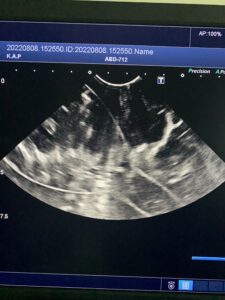

ですがちゃんと理解していないと、検査画像を見ても何がなんだかさっぱりわかりません!今日は少々マニアックですが、エコー検査の見方をご紹介します。

基本的にエコー検査とは全て「断面」で見ています。同じものでも、見る方向(断面)によっては全く違う様子で見えますよね。

下の写真に写っているエコー検査画像は、水の中に浮かんだ「あるもの」を2つの断面で見たものです。さて、「あるもの」とはなんでしょう?

※臓器ではありません。身近にある日用品(?)です。